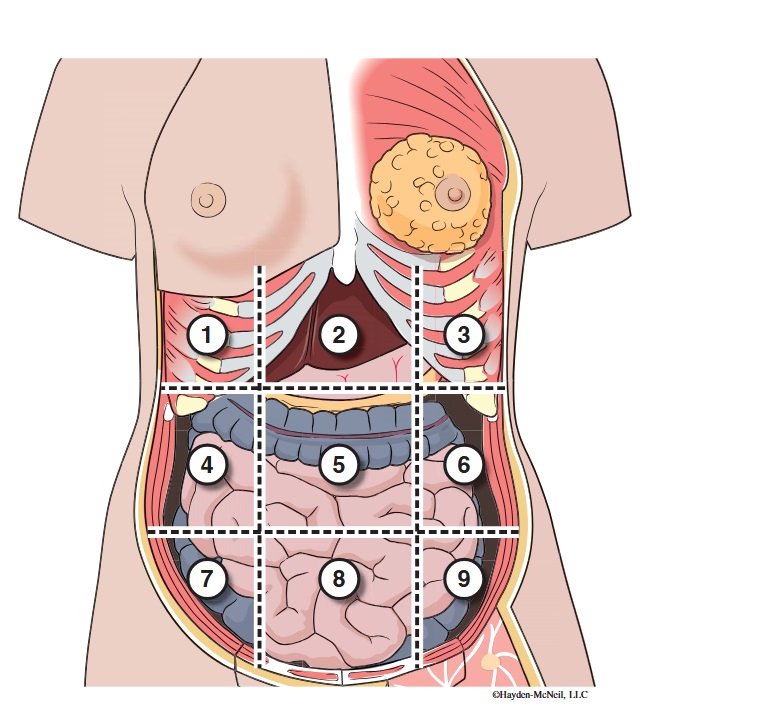

What abdominal region is labeled #1?

right hypochondriac

What abdominal region is labeled #2?

epigastric

What abdominal region is labeled #3?

left hypochondriac

What abdominal region is labeled #4?

right lumbar

What abdominal region is labeled #5?

umbilical

What abdominal region is labeled #6?

left lumbar

What abdominal region is labeled #7?

right iliac/ inguinal

What abdominal region is labeled #8?

hypogastric

What abdominal region is labeled #9?

left illiac/ inguinal

What organs are apart of the right hypochrondriac region?

right lobe of liver, gallbladder, right adrenal gland

What organs are apart of the epigastric region?

pyloric end of stomach, duodenum, pancreas

What organs are apart of the left hypochondriac region?

stomach, spleen, left adrenal gland

What organs are apart of the right lumbar region?

ascending colon, right kidney, portion of small intestine

What organs are apart of the umbilical region?

omentum, mesentery, small intestine

What organs are apart of the left lumbar region?

descending colon, left kidney, portion of the small intestine

What organs are apart of the right iliac/ inguinal region?

cecum of large intestines, appendix, right ovary

What organs are apart of the hypogastric region?

ileum, bladder, uterus

What organs are apart of the left iliac/ inguinal region?

sigmoid colon, left ureter, left ovary